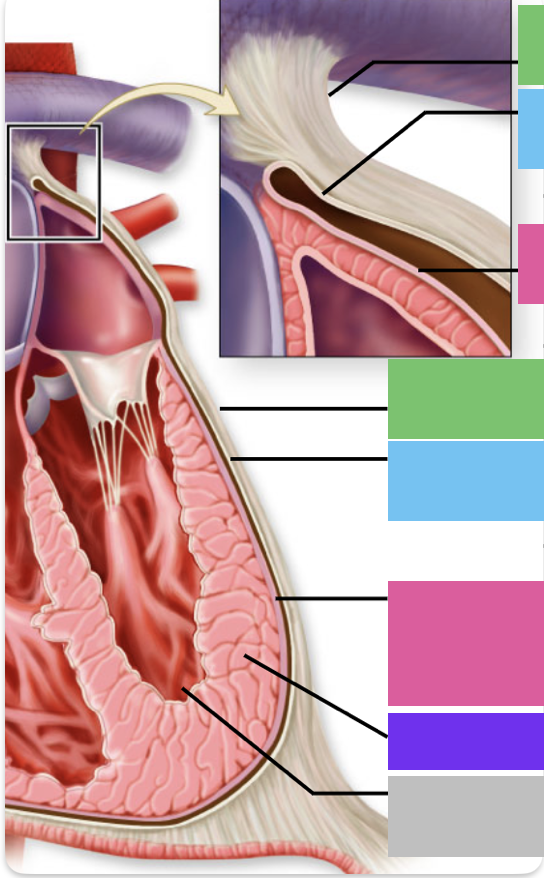

fibrous pericardium

blue

parietal pericardium

pink

visceral pericardium (connective tissue) / epicardium (muscle)

purple

myocardium

grey

endocardium